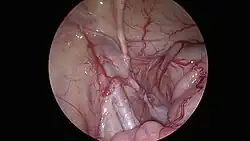

El tratamiento para el caballo criptorquido consiste en la aplicacion farmacologica de hormonas o realizar directamente una cirugia conocida como «orquiectomía». La cirugía conocida como “orquiectomía”, se realiza bajo anestesia general y consiste en la extracción de ambos testículos del animal, por medio de una incisión en el abdomen o la ingle ya que ahí se encuentra el testículo o los testículos no descendidos. En términos generales, el caballo termina siendo esterilizado o «Castrado» con el fin de eliminar la capacidad de reproducción del caballo y mejorar su comportamiento y rendimiento en las actividades como la equitación o el trabajo en el campo.